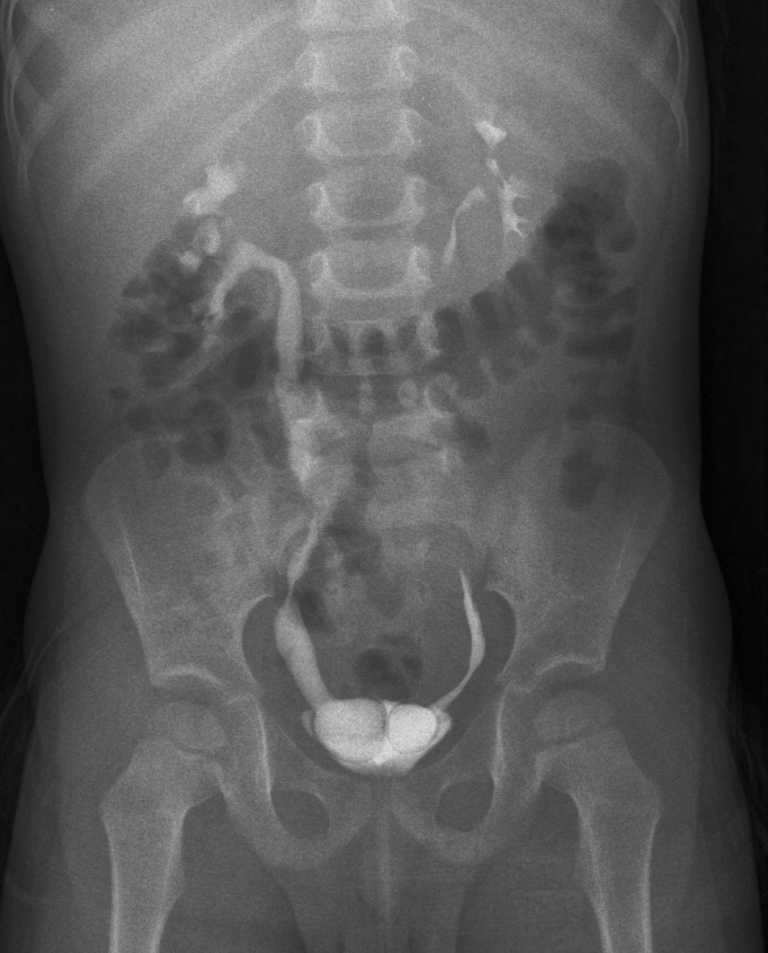

Внутривенная урография (или по др. экскреторная урография) – клинический, инструментальный метод рентгенодиагностики заболеваний мочевыделительной системы, основанный на способности почек выводить рентгеноконтрастное вещество с мочой. Аналогичным названием этого метода является экскреторная урография.

Исторически в рентгенологическом исследовании мочевыводящих путей, до появления и широкого внедрения компьютерной томографии (КТ), наиболее часто использовалась и продолжает применяться в настоящее время именно обычная внутривенная урография (ВУ). ВУ — рентгенологический тест, в котором контрастное вещество (также термин «рентгеновские краситель») вводится в вену пациента, который в последующем выделяется почками (отражая контуры и состояние паренхимы, фильтрационную функцию), проходимость мочеточников и контуры мочевого пузыря (нисходящая урограмма). Показания к применению ВУ разнообразны: боль в пояснице, кровь в моче (гематурия), установление локализации обструкции. Но следует проводить это исследование только после ультразвуковой диагностики (УЗИ), так как уже на этапе УЗИ может отпасть необходимость в проведении ВУ, как наиболее инвазивного исследования, связанного с введением контраста (который может вызвать аллергию или побочные действия).

При интерпретации урограмм обращают внимание на интенсивность теней паренхимы почек, их величину, форму, положение, равномерность плотности тени, время и интенсивность заполнения рентгеноконтрастным веществом чашечно-лоханочной системы, наличие тех или иных морфологических изменений верхних мочевых путей, состояние их тонуса и опорожнения, время контрастирования мочевого пузыря и особенности его конфигурации. На результаты экскреторной урографии оказывают влияние многие факторы, среди которых особое место занимают рефлекторные воздействия на почки и мочевые пути как эндогенного, так и экзогенного происхождения

Нормой считается нахождение правой почки на уровне 12-го и 3-го позвонков, а почки левой — на уровне 11-го и 2-го. С правой стороны двенадцатое ребро находится на уровне верхней доли почки, с левой — пересекает ее в средней части. Наполненный пузырь отображается на снимке в виде тени эллиптической формы. Контуры почек и мочевого пузыря ровные, не имеют патологических изменений. Тени на изображении однородные. Если мочеточники находятся в нормальном состоянии, они на снимке не отображаются. На снимках также присутствует изображение мышц поясницы в виде усеченных пирамид, их вершина находится на уровне 12-го грудного позвонка.

Высокая плотность затемнений почек может быть свидетельством пиелонефрита и паранефрита, отсутствующие или стертые контуры могут быть признаками гигантской кисты почки, онкологической гематомы или опухоли.